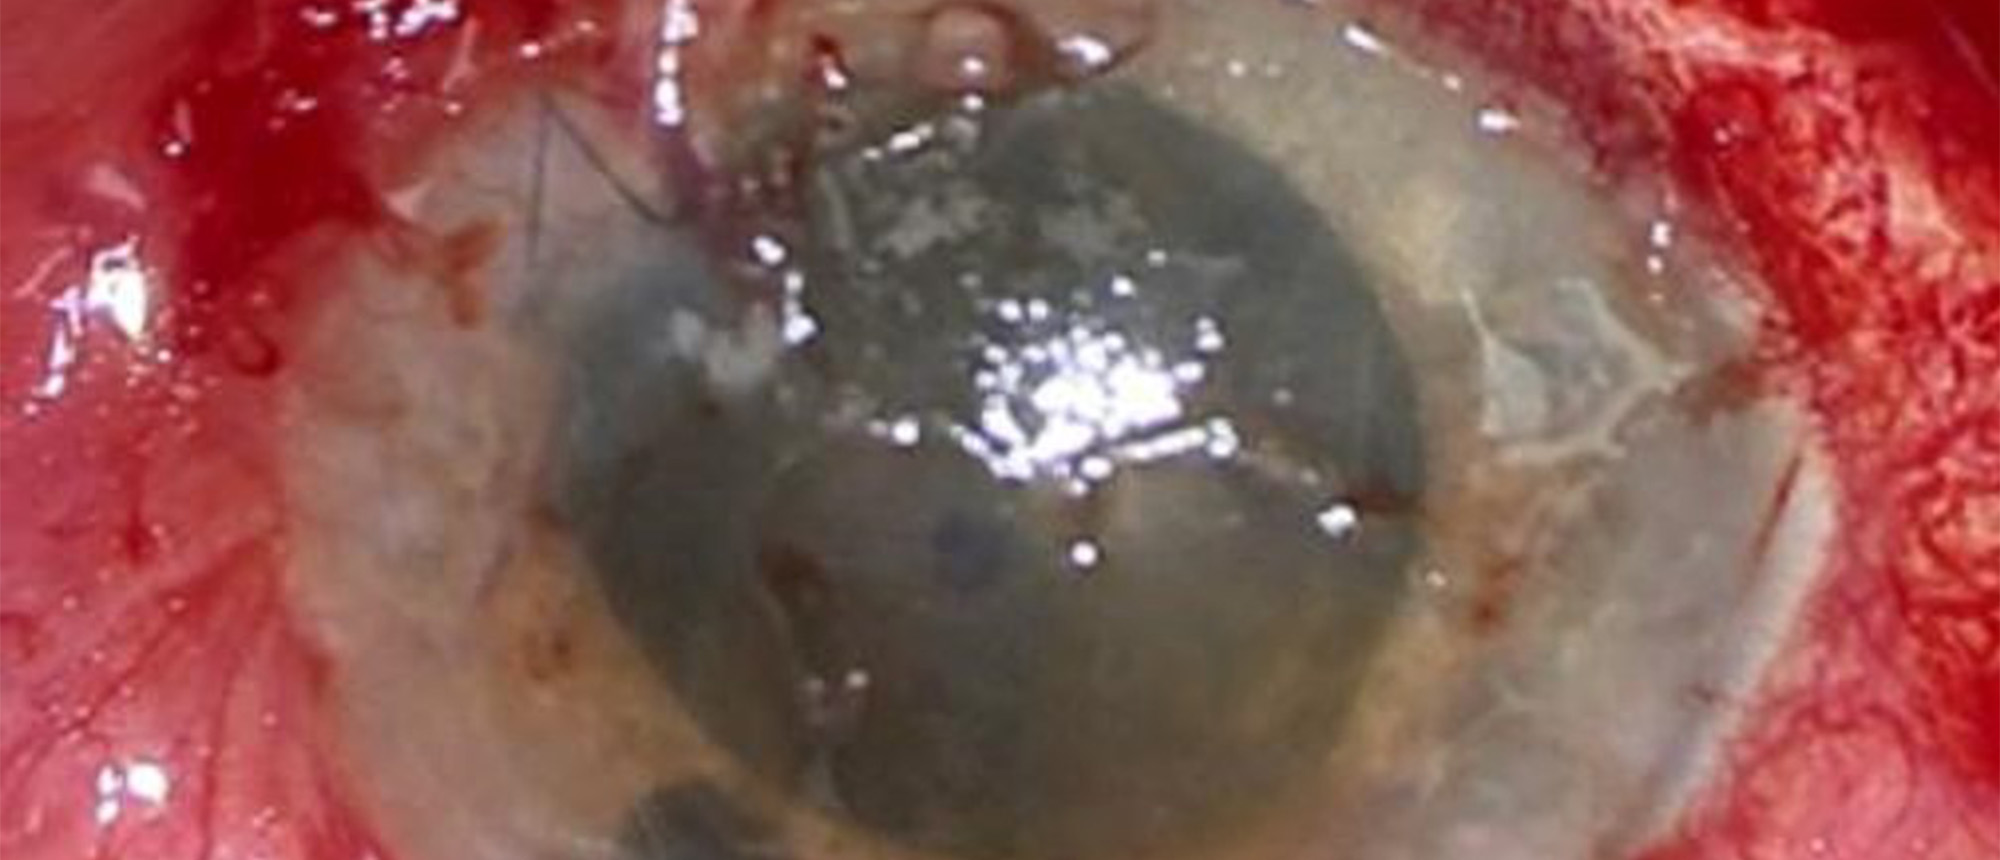

Intraocular Helminth

Original Contributor(s): Spencer C. Barrett, MD; Kisha Kalra, MD; Jonathan D. Tijerina, MD, MA

Presenter/Faculty: Barrett, Kalra, Tijerina